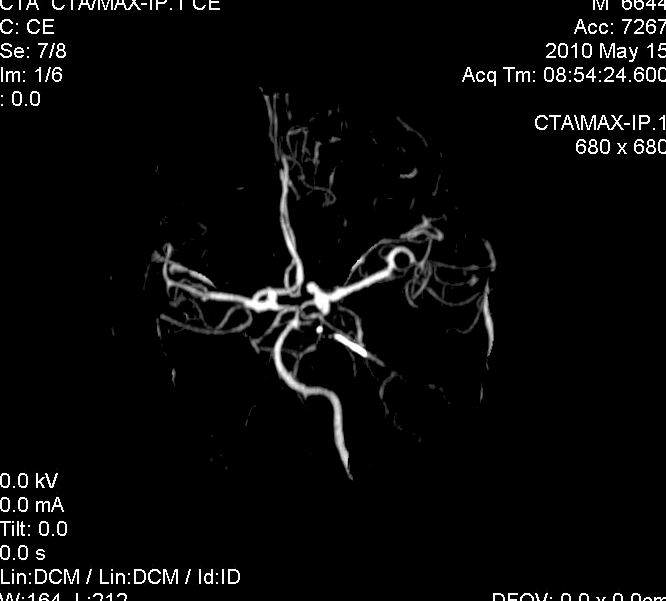

男.60岁,渐进性意识不清,ct检查双侧额颞顶部硬膜下血肿,开颅术后行脑血管cta,大脑中动脉起始部见一瘤状血管扩张。请各位老师留下宝贵意见

太常见了,报动脉瘤就可以

符合动脉瘤表现。

符合动脉瘤表现。

动脉瘤。

颅内动脉瘤。

后重建做得不是很好看,要将维蒂斯环充分显示,最好在增加一个mip。这样不好定位。

小动脉瘤

典型

符合动脉瘤的表现

动脉瘤

符合动脉瘤表现。

小动脉瘤

典型